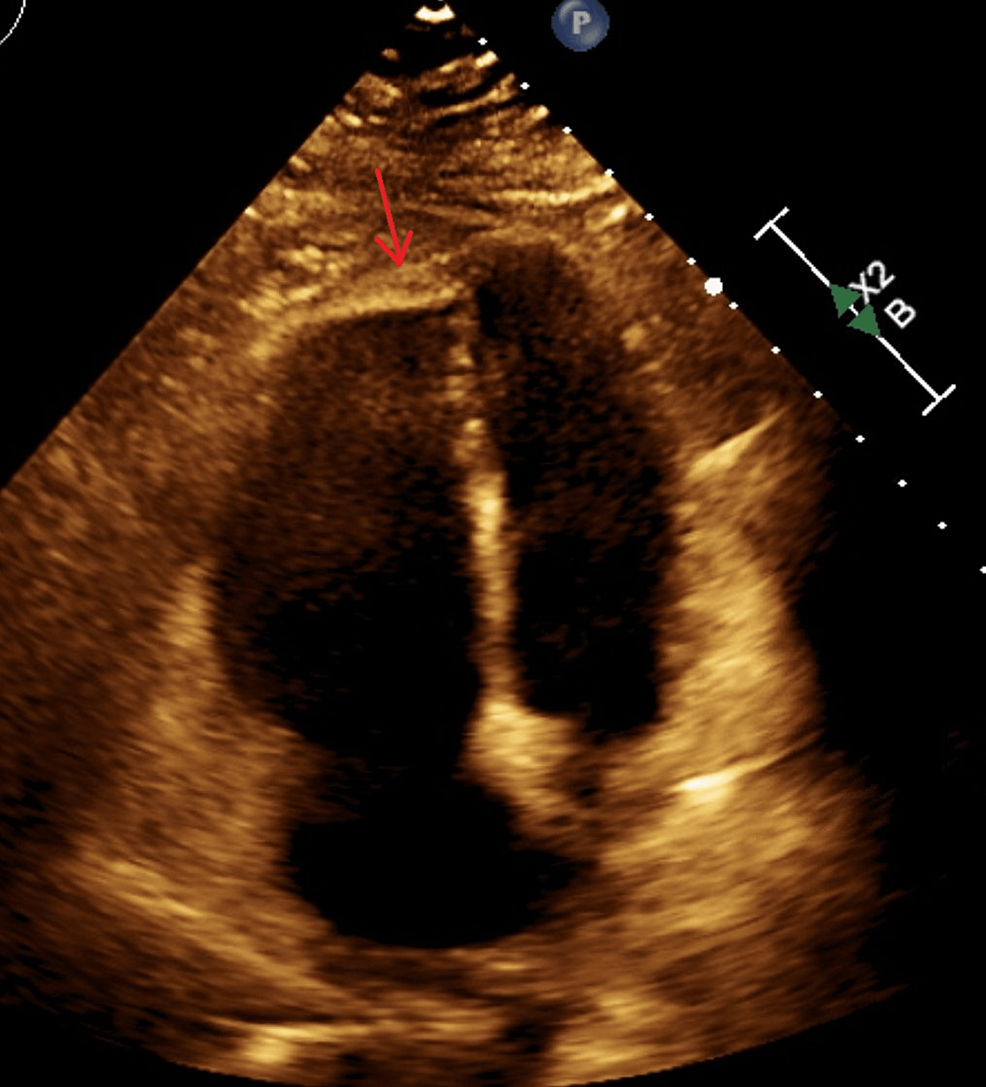

From www.cureus.com

Persistent Peril Recurrent Deep Vein Thrombosis and Pulmonary Embolism Protein S Deficiency Pulmonary Embolism Protein s deficiency is an inherited thrombophilia associated with an increased risk of thromboembolism. Conditions such as protein s deficiency, resulting from genetic mutations, are encompassed within this category of causative. Free and total protein s deficiency was not associated with venous. Having this deficiency puts you at risk for a blood clot in your leg or arm veins that’s. Protein S Deficiency Pulmonary Embolism.